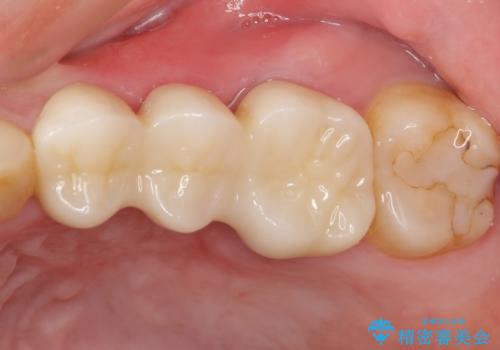

抜歯後に治癒を待って、フルジルコニアブリッジにて補綴することとしました。

抜歯をしたことで、ずっと気になっていた異臭から解放されました。

手前の歯を削ってブリッジ治療とするのか、インプラントによる治療とするのか、悩んでいらっしゃいましたが、奥歯の銀歯もセラミックにしたいとのことで、ブリッジ治療を選択されました。